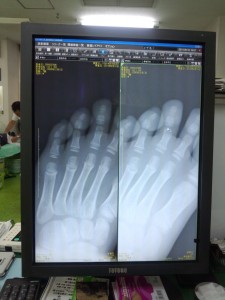

コウキ君は、「痛い、痛い」と言って、さわらせてくれません。左足中指が開いて、小指側に傾いています。右足指と比べて明らかに違います。打撲だけだったらいいのですが、骨折しているかもしれません。連休なので、病院にすぐに行くこともできないし、救急で行くほどでもないようだし・・・と、しばらく冷やしながら、様子を見ることにしました。

「コウキ、中指の3番目の骨が、ポキッと折れてた!!」

「やっぱりか~。」と、もう少し早く救急病院に連れて行っておけばよかったと反省。可愛そうに、足の指を引っ張って、2回も整復してもらい、簡易ギブスで固定してもらったようです。帰ってきたら、ベビーカーで学校まで送っていきました。学校の帰りには、ベビーカーでは可哀想と、学校から車椅子を貸してくださいました。明日から、これで登下校します。